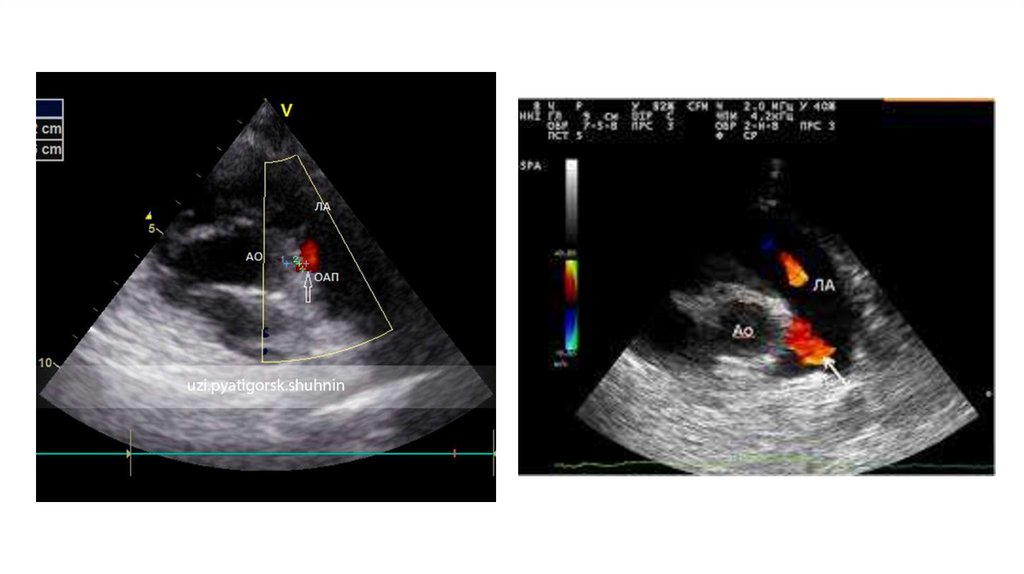

7.  Инструментальная диагностика

Инструментальная диагностика

• ЭхоКГ – золотой стандарт. Ключевые задачи:

1.Визуализация протока: Доступы – высокий парастернальный

по короткой оси, супрастернальный.

2.Измерение диаметра: В В-режиме или ЦДК в самом узком

месте.

3.Оценка сброса: ЦДК и спектральный допплер (непрерывный

турбулентный поток).

4.Оценка гемодинамической значимости:

1. Легочная гиперперфузия: Размер ЛП (ЛП/Ао > 1.4-1.5), размер ЛЖ

(КДР ЛЖ).

2. Системная гипоперфузия: Оценка диастолического кровотока в

нисходящей/брюшной аорте (антеградный/нулевой/ретроградный).

5.Исключение сочетанной патологии: Коарктации аорты,

других ВПС.